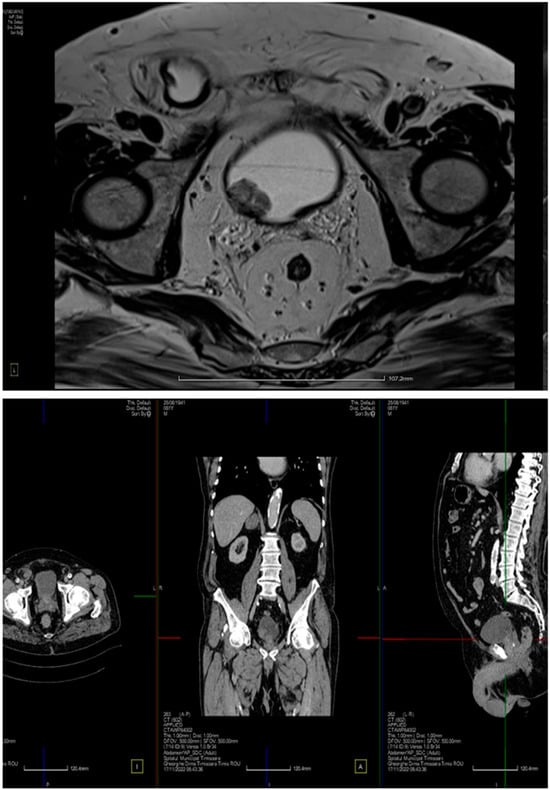

2. Case Presentation